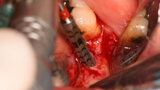

Rehabilitace Straumann